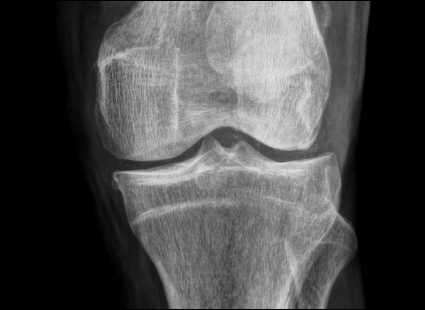

La enfermedad relacionada con la inmunoglobulina G4 (IgG4), conocida como "IgG4-related disease" en inglés, es un trastorno sistémico de causa desconocida que se caracteriza por una fibroinflamación altamente característica. Esta…